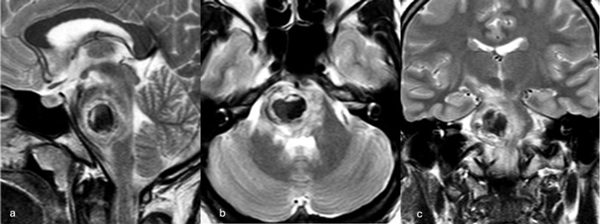

Figura 3. RM preoperatoria de encéfalo. Se evidencia una lesión única intraaxial centrada en puente y pedúnculo cerebeloso derecho, sugerente de un cavernoma roto. A, B y C) Imágenes ponderadas en T2 en cortes sagital, axial y coronal, respectivamente, donde se observa un importante hiperintensidad perilesional, sugerente de edema.